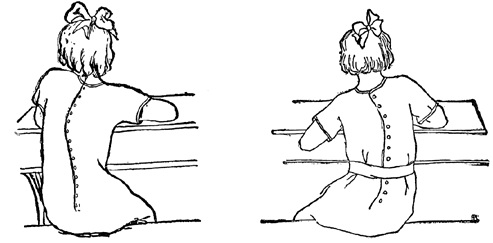

- Postura defectuoasă în special la masă și atunci când lucrează la birou